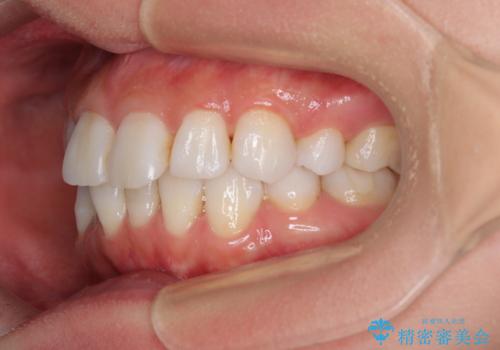

矯正治療の後戻り インビザラインで短期間矯正治療

- 上下前歯の後戻りを気にして来院された患者様です。

インビザラインでの治療を希望されていて、デコボコの程度が中等度であり、安価なパッケージにて対応可能と判断されたため、インビザライン・モデレートを用いて矯正治療を行うこととしました。

インビザライン・モデレートは、製作できるアライナーの枚数に制限があるため、移動可能な量に限りがあるものの、インビザライン・ライトよりも枚数が多いため、幅広い症例に対応可能です。